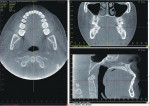

It is important to note that the various CBCT units come with standard viewing software, which will allow the dentist to examine the selected area of interest in all three planes: axial, coronal, and sagittal (Figure 5).

Basic enhancements include zoom or magnification and visual adjustments to narrow the range of the displayed gray scale and contrast levels within the window, as well as cursor-driven measurements and annotations. Third party software programs will provide enhancement features that will allow the image to render with color, highlighting greater detail to the volume. These programs usually have additional functions, such as mandibular nerve location and implant planning (Figure 6).